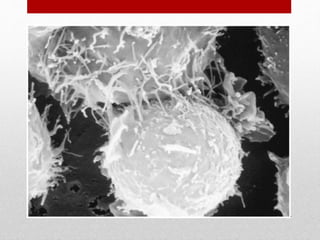

Cytotoxic T cells(CD-8T cells)-

• Capable of killing target cells to which they bind.

• Formed in response to viral infection & graft

from dissimilar member.

• Are cytotoxic to host cells infected with virus;

graft tissues ;tumor cells.

• Mech. Of action-

• Binding of effector cell to target cells through

specific receptors.(ca+ independent stage)

• Changes occurs in target cell which causes lysis.

• Destruction of target cell d/t release of perforins

which puncture target cell